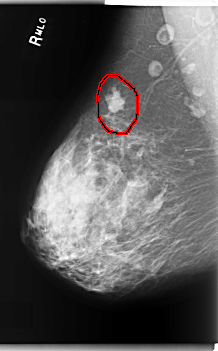

C_0208_1.RIGHT_MLO

RIGHT_MLO LINES 5960 PIXELS_PER_LINE 3696 BITS_PER_PIXEL 12 RESOLUTION 50 OVERLAY

FILE: C_0208_1.RIGHT_MLO.OVERLAY

TOTAL_ABNORMALITIES 1

ABNORMALITY 1

LESION_TYPE MASS SHAPE IRREGULAR MARGINS MICROLOBULATED

ASSESSMENT 5

SUBTLETY 5

PATHOLOGY MALIGNANT

TOTAL_OUTLINES 1

BOUNDARY